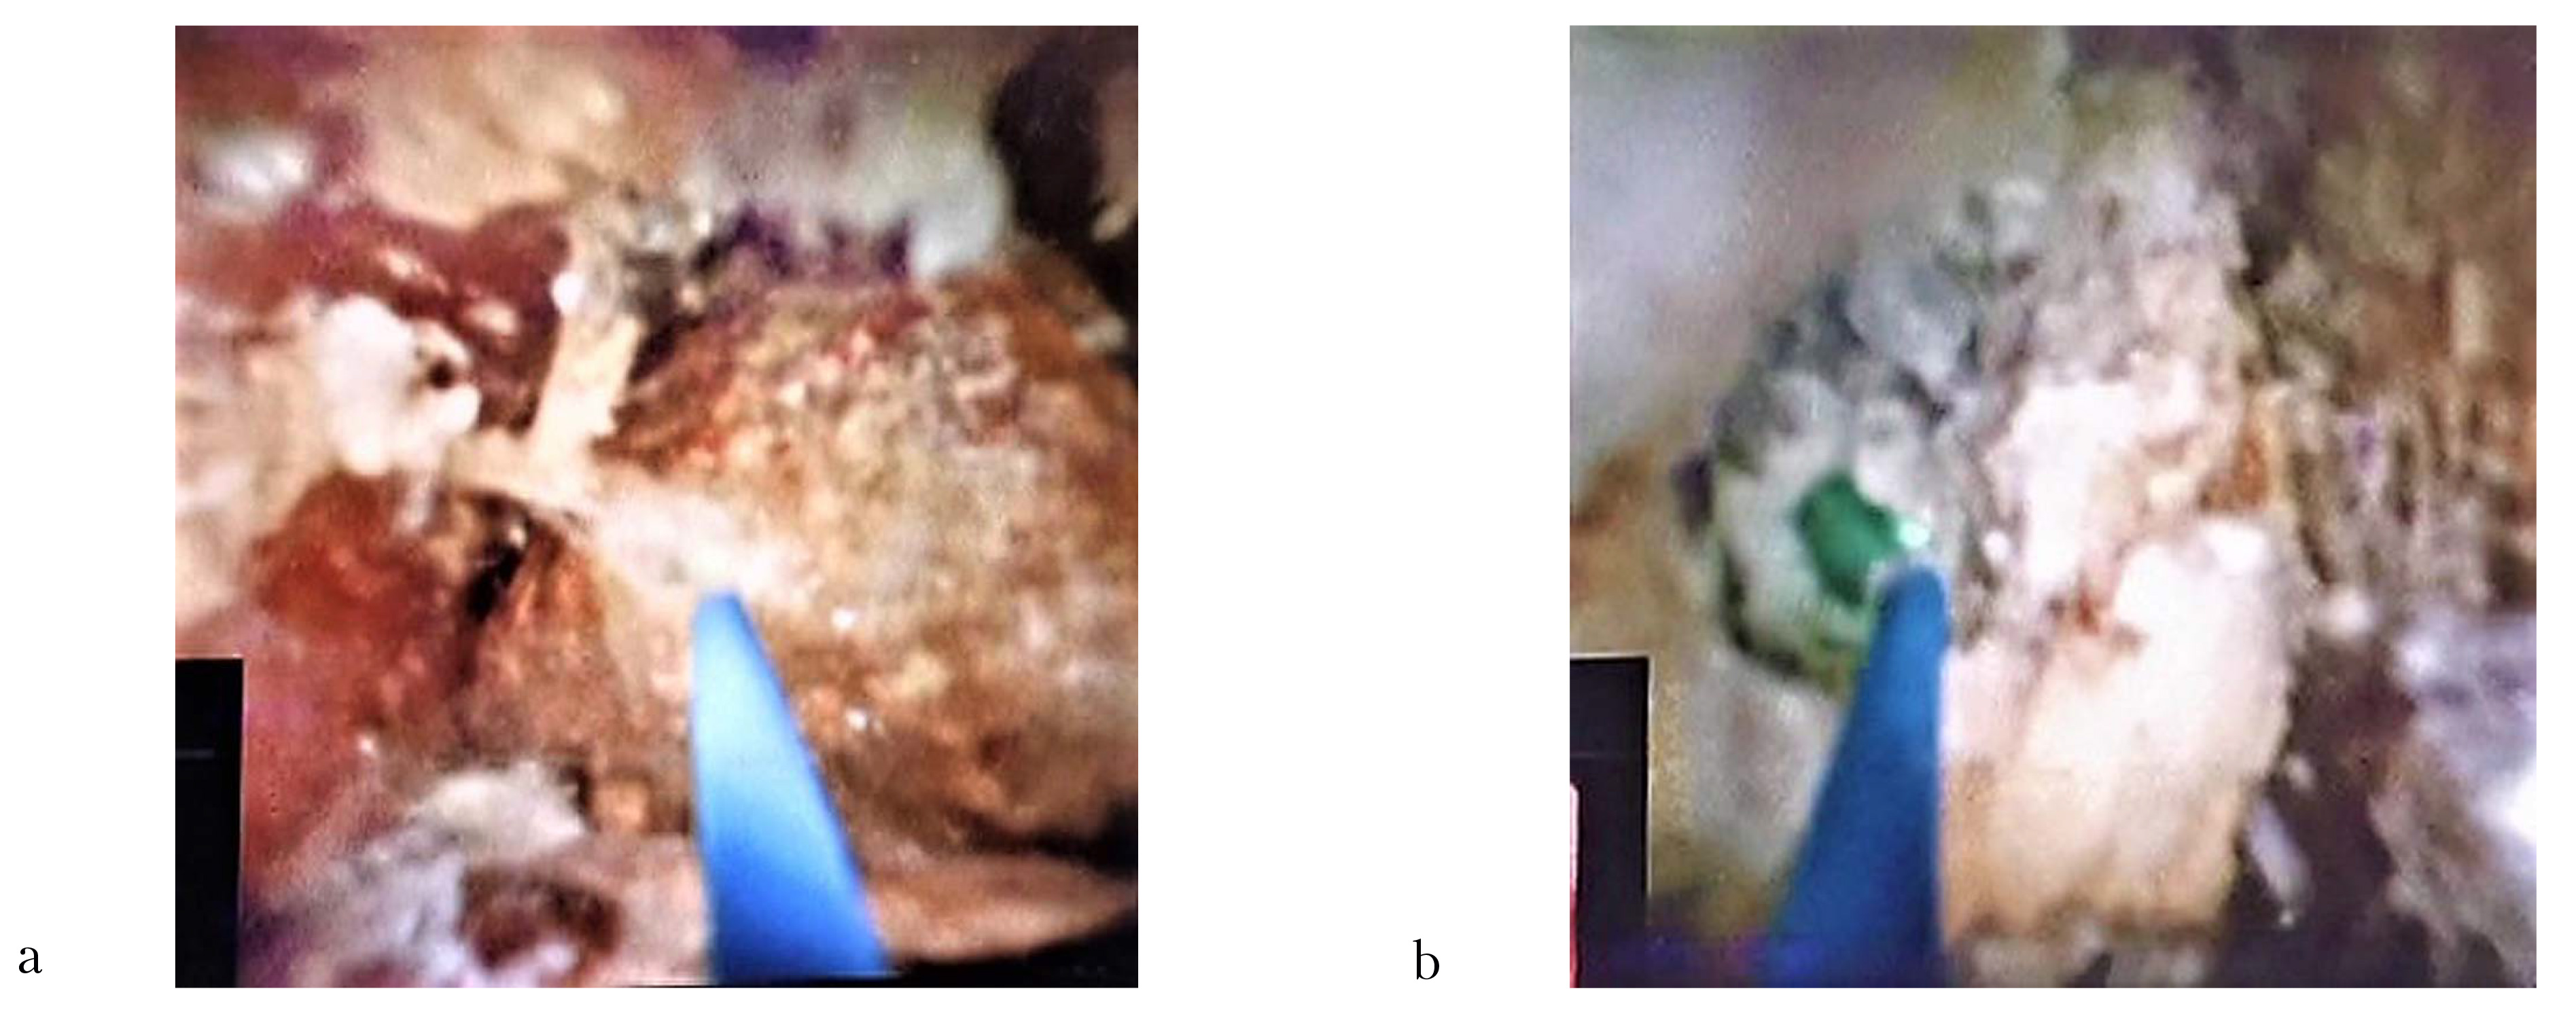

После удаления назобилиарного дренажа и ретроградной канюляции ОЖП с помощью аппарата Spy-Glass DS II фирмы Boston Scientific (США) была проведена холангиоскопия, при которой была визуализирована неровная, фрагментарно изъеденная часть дистального края конкремента светло-коричневого цвета, занимающего практически весь просвет общего желчного протока. После заполнения просвета билиарного тракта стерильным физиологическим раствором через инструментальный канал холедохоскопа было проведено лазерное волокно диаметром 200 микрон. После этого с использованием тулиевого лазера в режиме «Распыление» была выполнена литотрипсия нижнего полюса камня с постепенным увеличением параметров частоты с 40 до 60 Гц и средней мощности с 8 до 12 Вт при энергии в импульсе 0,2 Дж (рис. 4a). После разрушения поверхностных слоев конкремента визуализировалось его наиболее плотное «ядро» светлого цвета (рис. 4b).

Рис. 4: a — разрушение нижнего полюса конкремента (эндофото); b — визуализирована центральная часть конкремента (эндофото)

Затем с помощью лазерного волокна большего диаметра (400 микрон) в попеременно используемых режимах «Распыление» и «Попкорнинг» была разрушена центральная часть конкремента и выполнена его фрагментация (размеры полученных осколков составили от 4 до 12 мм) (рис. 5). Во время вмешательства были отмечены единичные кратковременные (не более 1 секунды) попадания лазерного луча на стенку ОЖП, при этом какихлибо изменений со стороны слизистой холедоха выявлено не было.

Рис. 5: a — разрушение центральной части конкремента (эндофото); b — один из фрагментов разрушенного конкремента (эндофото); c — разрушенный на фрагменты крупный конкремент (холангиограмма)